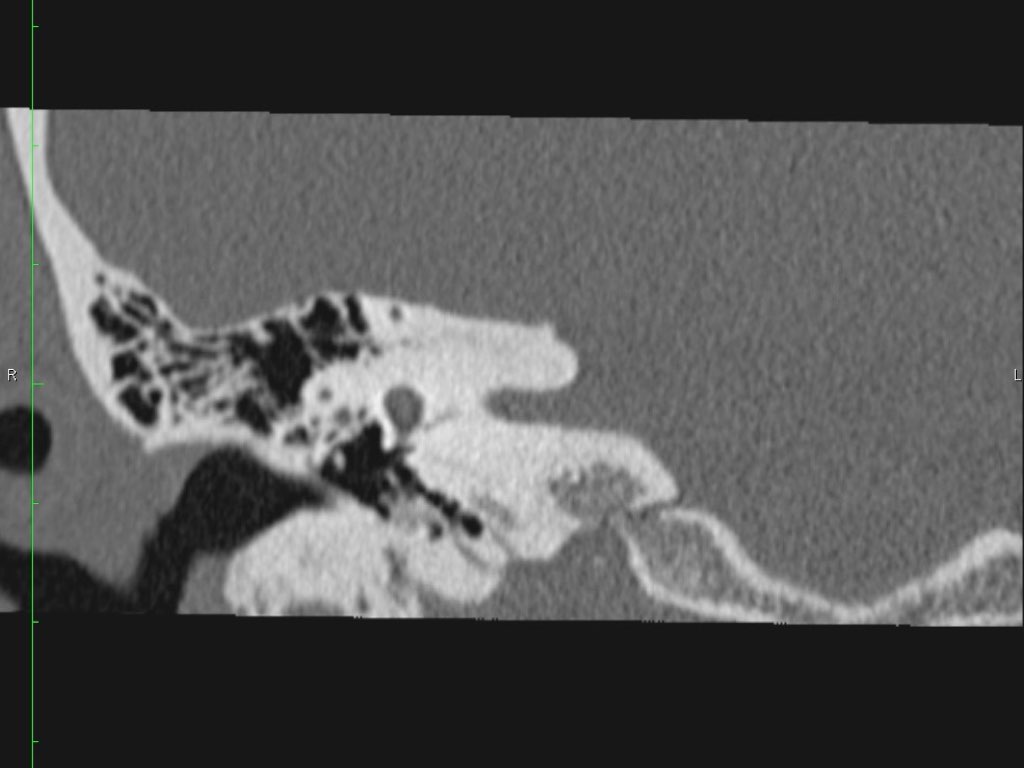

Hình ảnh một bệnh nhân có cholesteatoma.

Có một khối mô mềm ở vùng thượng nhĩ.

Lưu ý hình ảnh thủng màng nhĩ (mũi tên vàng) và bào mòn ống bán khuyên ngoài (mũi tên đỏ).

Scutum bị tù mòn.